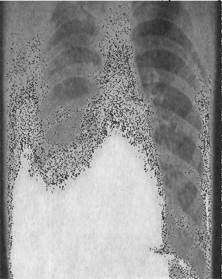

66. Больной 30 лет, без вредных привычек обратился с жалобами на повышение температуры, до 380С, малопродуктивный кашель, общую слабость. Заболел остро в течении 3 дней. При обследовании на рентген-снимке выявлены следующие изменения:

Какие антибактериальные средства являются препаратами первого ряда при лечении данного больного?